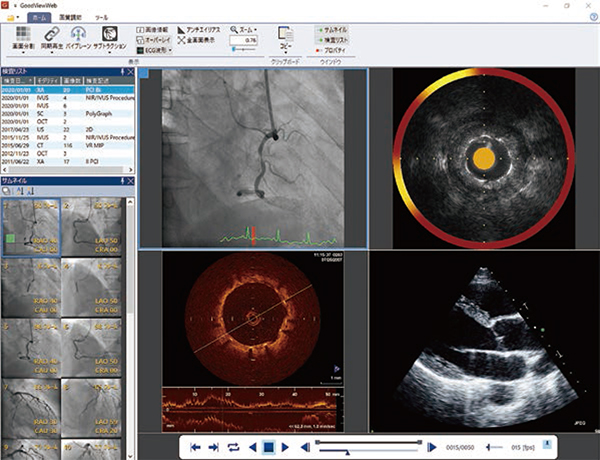

まず,注目すべきは,院内におけるオリジナルDICOM画像の高速配信である。一般的なPACSでは,医療機関内の電子カルテなどのHIS端末への画像配信にJPEGなどの圧縮画像を用いることが多い。これにより高速での画像配信は可能であったが,一方で画質は妥協せざるを得なかった。しかし,GOODNET 7では,DICOM形式のデータを高速に配信可能。Webブラウザを用いるGOODNETWebでも,診断レベルのDICOM画像を閲覧できるようになった。DICOMビューワであるGoodViewだけでなく,GOODNETWebでも同様にDICOM画像を扱えるようになったことで,医療機関内各所の電子カルテなどのHIS端末から読影を行えるほか,IVUSなどの距離・角度・面積の簡易計測も可能なため,ユーザーにとっての利便性が大いに向上すると期待される。

「GOODNET 7」はDICOM画像をHIS端末の「GOODNETWeb」に高速配信可能

このほかにもGoodViewでは,過去検査画像やレポートの分割表示といったビューワとしての機能に加えて,インターベンションにおいて重要となるIVUSやOCTの長軸画像構築,簡易計測といった手技を支援する機能を搭載している。